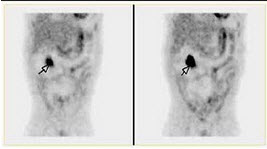

94、单项选择题

17岁男孩,突发黑便3天,行99TcmO3腹部显像如图,正确的诊断是()

A.箭头所示异位胃粘膜

B.箭头所示Barrett食管

C.箭头所示肠重复畸形

D.箭头所示Meckel憩室

E.以上都不对

点击查看答案